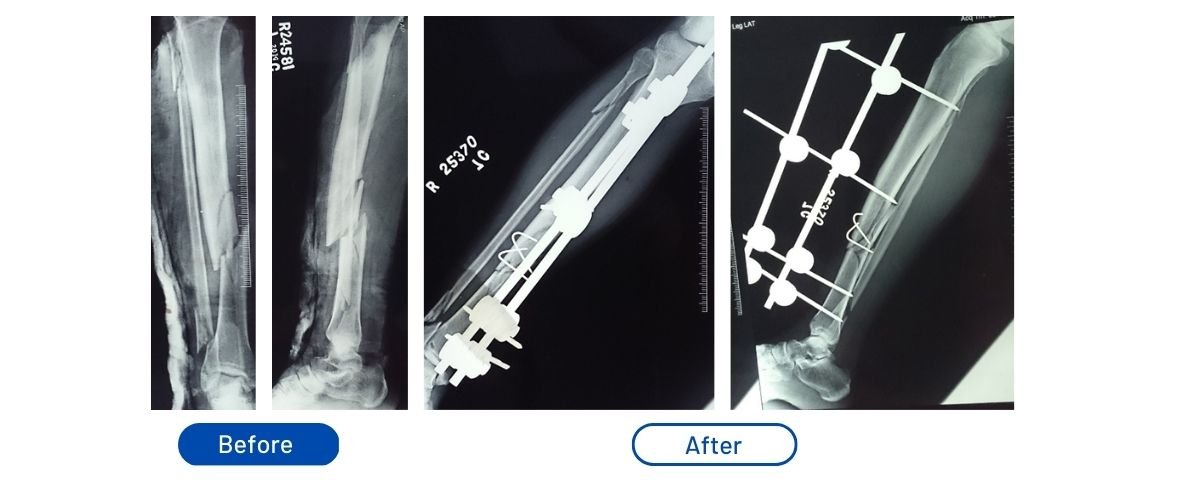

Comminuted Tibia Fracture